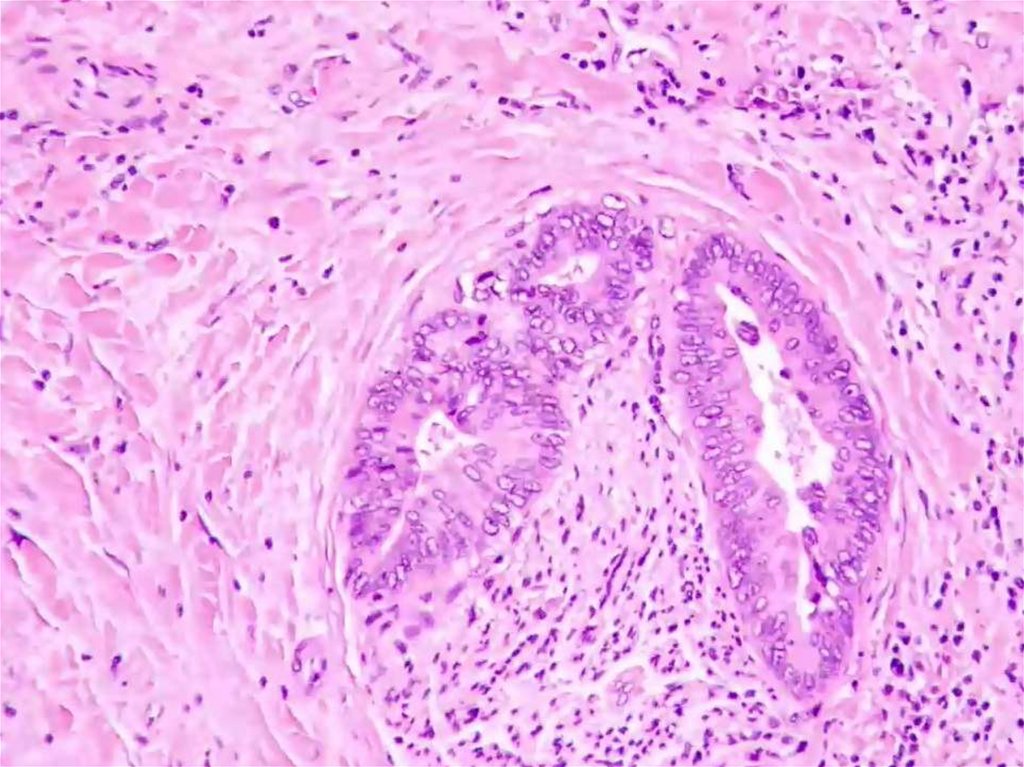

Cholangicarcinoma